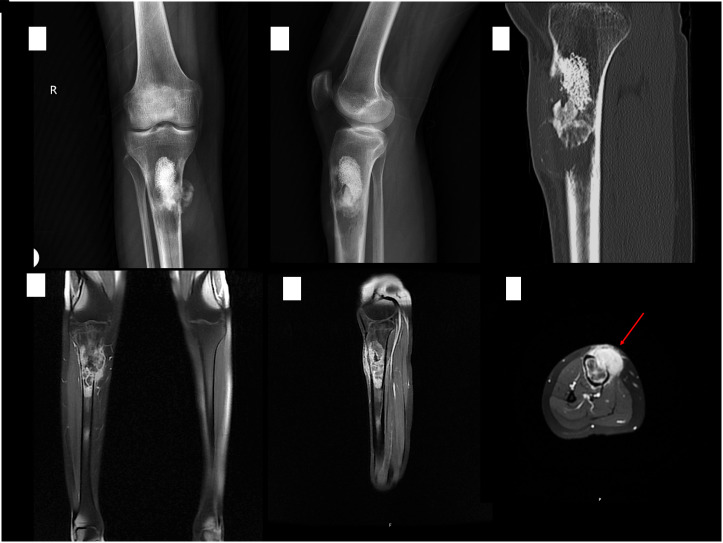

巨细胞富骨肉瘤(GCRO)是一种罕见的骨肉瘤变体,具有不寻常的放射学和组织病理学特征,使其诊断具有挑战性。GCRO最关键和最不寻常的特征是它具有纯粹的溶骨外观。因此,GCRO病例往往因误诊而延误诊断或错误治疗。这对这些患者的预后有负面影响。在本研究中,提出了3例年轻成人病例。第一个病例描述了一位年轻的女性患者,由于误诊为巨细胞骨肿瘤而进行了多次刮除,第二个病例描述了一位年轻的男性患者被误诊为动脉瘤性骨囊肿而延误诊断。最后的病例报告描述了一位年轻女性,她被早期诊断,及时治疗,预后良好。本报告中1例预后不良的病例采用截肢治疗,另1例存活并有多发转移灶。在这种情况下,误诊或延误诊断导致预后不良。为了做出诊断,有必要了解并怀疑这种罕见变异的放射学特征。当处理年轻成人纯干骺端溶骨性病变时,巨细胞富骨肉瘤应作为鉴别诊断选择之一。为了避免误诊或延误,有必要了解并怀疑这种罕见的变异。证据等级:IV级,治疗性研究。

Giant cell-rich osteosarcoma (GCRO) is a rare variant of osteosarcoma with unusual radiological and histopathological features that make its diagnosis challenging. The most critical and unusual feature of GCRO is that it has a purely osteolytic appearance. Therefore, GCRO cases are frequently subject to delayed diagnosis or incorrect treatment owing to misdiagnosis. This negatively affects the prognosis of these patients. In this study, 3 young adult cases are presented. The first case describes a young female patient who underwent repeated curettages due to a misdiagnosis of a giant-cell bone tumor, and the second case describes a delay in diagnosis in a young male patient who was misdiagnosed with an aneurysmal bone cyst. The final case report describes a young woman who was diagnosed early, treated promptly, and had a good prognosis. One of the poor prognosis cases in this report was treated with amputation, and the other was alive with multiple metastases. Misdiagnosis or delayed diagnosis leads to a poor prognosis in such cases. To make a diagnosis, it is necessary to have knowledge and to be suspicious of the radiological features of this rare variant. Giant cell-rich osteosarcoma should be among the differential diagnosis options when dealing with pure metaphysiodiaphyseal osteolytic bone lesions in young adults. To avoid misdiagnosis or delay, it is necessary to have knowledge and to be suspicious of this rare variant. Level of Evidence: Level IV, Therapeutic study.